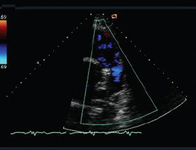

Ecocardiografia com Doppler em um paciente com regurgitação pulmonar após reparo de tetralogia de Fallot, revelando via de saída do ventrículo direito não obstruída. O paciente tem ventrículo direito restritivo

De: Chaturvedi RR, Redington AN. Heart. 2007 Jul;93(7):880-9; usado com permissão